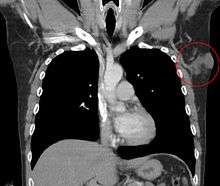

| Histopathological image of dermatofibrosarcoma protuberans. Local recurrence long after the first excision. H&E stain | |